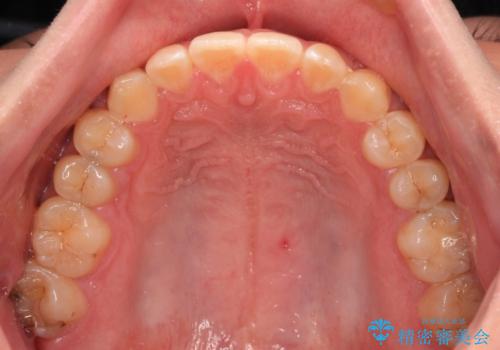

空隙歯列を閉じる 舌のトレーニングとワイヤー矯正

- 上下前歯の隙間を気にして来院された患者様です。

飲み込みや話をするときに舌を突出させる癖が強くあり、それが原因でスペースが空いていました。

舌癖を改善するためのトレーニングを行いながら、ワイヤー装置を用いて前歯の隙間を閉じていくこととしました。

舌の突出癖がなかなか改善されず、治療期間は当初予定よりも大分長くなりました。

装置除去を予定していた日に、油断されたのか1mmほどのスペースを作ってしまったため、除去が3ヶ月延長されたことで、舌のトレーニングの重要性を理解していただきました。

装置除去後もトレーニングを継続されているようで、後戻りによるスペースは今のところ認められておりません。